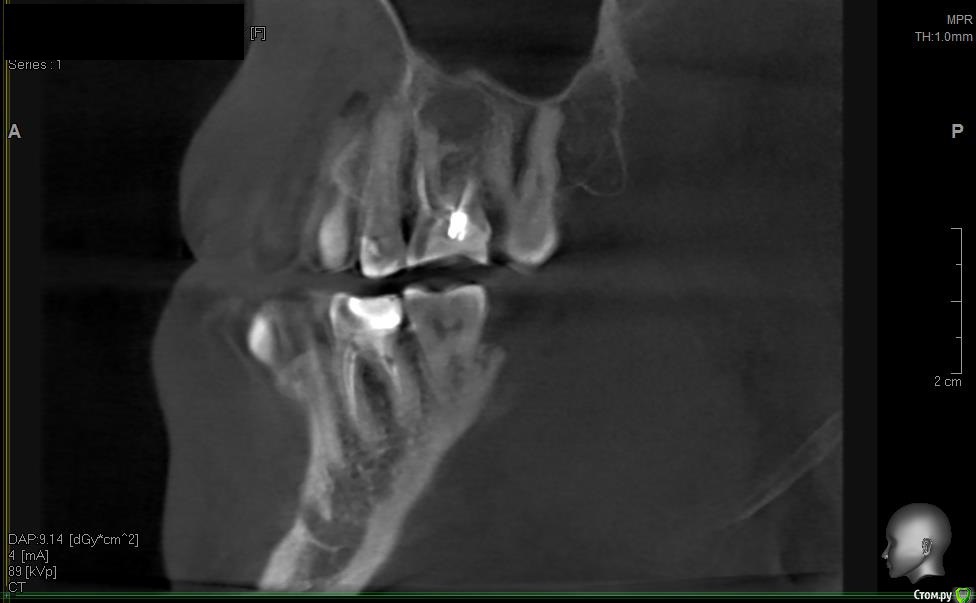

solitary Опубликовано 10 апреля, 2017 Поделиться Опубликовано 10 апреля, 2017 Доброго времени суток! Мое желание исправить прикус превратилось в ходьбу по врачам - от терапевта, до оториноларинголога и хирурга. На ОПТГ (прилагаю) ортодонту не понравилось темное пятно над верхней правой 6-кой. Т.к. хирурга у них в клинике нет, то на консультацию отправили к ортопеду-имплантологу. Предварительный диагноз - киста. Сделали КТ (скриншоты прилагаю).Диагноз подтвердили, но на всякий случай отправили к ЧЛ-хирургу. Тот с КТ от Пикассо не работает (компьютер слабый), но по моим скриншотам также считает, что это киста. Стоматолог врач-терапевт высшей категории вскрыла пломбу и увидела хорошо пролеченные каналы, плюс сделала прицельный снимок 6-ки, который кисту в зоне корня зуба не выявил (даже намека нет). Хотят отправить к оториноларингологу, так как, если верить КТ, киста у границы гайморовой пазухи и консультация ЛОР-врача будет не лишней. Хотелось бы послушать мнение опытных хирургов.-------ОПТГ http://radikal.ru/big/hq2s2k2k9uadn Ссылка на комментарий

solitary Опубликовано 11 апреля, 2017 Автор Поделиться Опубликовано 11 апреля, 2017 (изменено) Альтернативный способ установки аппарата нашли (цеплять за 5-ки), но меня сейчас больше волнует судьба зуба. Каналы хорошо пролечены, штифт стоит просто на века. При вскрытии пломбы никаких неприятных запахов, которые характерны для кистозного воспаления. Клинических показаний вроде нет (я про отечность десны, воспаление лимфоузлов, повышение температуры тела и т.п.) Очень бы хотелось сохранить зуб Изменено 11 апреля, 2017 пользователем solitary Ссылка на комментарий

Irouil Опубликовано 11 апреля, 2017 Поделиться Опубликовано 11 апреля, 2017 Повторюсь - вскрытие пломбы не при чем. Киста в кости, пломба в зубе. Между кистой и пломбой - закрытый наглухо (судя по кисте у корня - не совсем наглухо) длинный корневой канал. Навряд кто-то возьмется лечить этот зуб гарантийно. Но если Вы готовы рисковать своим временем и финансами - шансы есть. Ссылка на комментарий

DmitrySH Опубликовано 12 апреля, 2017 Поделиться Опубликовано 12 апреля, 2017 Да нет, сама по себе повторная эндодонтия бывает часто, но наши терапевты всегда предупреждают о возможной неудаче. Но мне кажется шансы какие-то тут есть. Удаление конечно может иметь место, если в ходе лечения выявляются:1. Разрушение зуба не подлежащее лечению.2. Погрешности проведенного ранее лечения, не позволяющие адекватно обработать каналы. Если зуб "целый" и каналы правильно обработаны и запломбированы, то очень высок шанс на благоприятный исход.Размер очага воспаления не играет существенной роли. А неудача может быть и при лечении обычного пульпита, никто не застрахован. Ссылка на комментарий